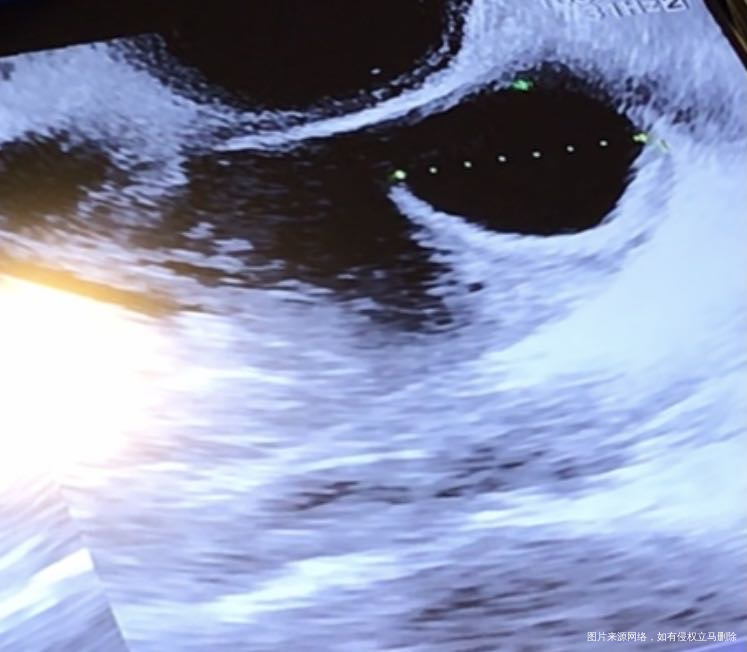

第一张图排卵前卵泡20毫米,第二张图排卵后第六天b超,卵泡外观扁了可是还有15毫米存在,本月就这一个大卵泡,请问这是排卵了吗?排完后这15毫米的东西为什么还存在?这是黄体吗?